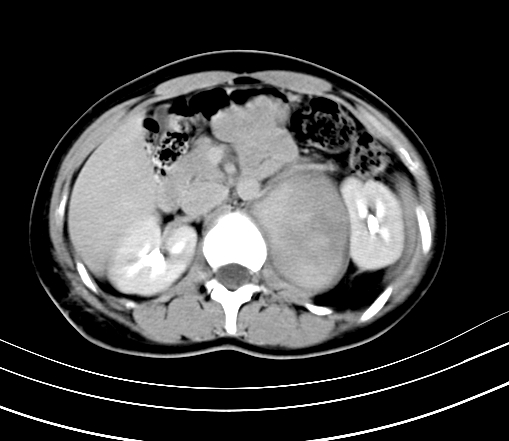

延时5分钟